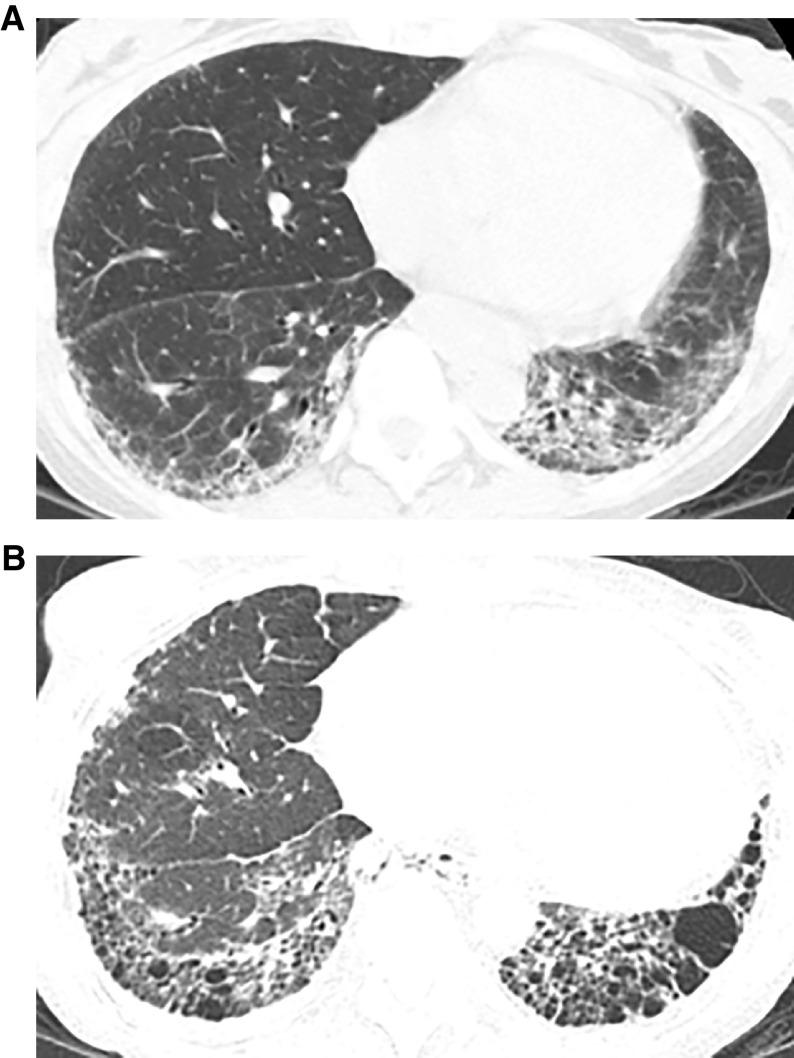

This American Thoracic Society, European Respiratory Society, Japanese Respiratory Society, and Asociación Latinoamericana de Tórax guideline updates prior idiopathic pulmonary fibrosis (IPF) guidelines and addresses the progression of pulmonary fibrosis in patients with interstitial lung diseases (ILDs) other than IPF. A committee was composed of multidisciplinary experts in ILD, methodologists, and patient representatives. ) Update of IPF: Radiological and histopathological criteria for IPF were updated by consensus. Questions about transbronchial lung cryobiopsy, genomic classifier testing, antacid medication, and antireflux surgery were informed by systematic reviews and answered with evidence-based recommendations using the Grading of Recommendations, Assessment, Development and Evaluation (GRADE) approach. ) Progressive pulmonary fibrosis (PPF): PPF was defined, and then radiological and physiological criteria for PPF were determined by consensus. Questions about pirfenidone and nintedanib were informed by systematic reviews and answered with evidence-based recommendations using the GRADE approach. ) Update of IPF: A conditional recommendation was made to regard transbronchial lung cryobiopsy as an acceptable alternative to surgical lung biopsy in centers with appropriate expertise. No recommendation was made for or against genomic classifier testing. Conditional recommendations were made against antacid medication and antireflux surgery for the treatment of IPF. ) PPF: PPF was defined as at least two of three criteria (worsening symptoms, radiological progression, and physiological progression) occurring within the past year with no alternative explanation in a patient with an ILD other than IPF. A conditional recommendation was made for nintedanib, and additional research into pirfenidone was recommended. The conditional recommendations in this guideline are intended to provide the basis for rational, informed decisions by clinicians.

美国胸科学会、欧洲呼吸学会、日本呼吸学会和拉丁美洲胸科学会更新了特发性肺纤维化(IPF)指南,涵盖了除 IPF 以外的间质性肺疾病(ILD)患者肺纤维化的进展。一个委员会由ILD 的多学科专家、方法学家和患者代表组成。

• 更新 IPF:通过共识更新了 IPF 的放射学和组织病理学标准。关于经支气管肺冷冻活检、基因组分类器检测、抗酸药物和抗反流手术的问题,通过系统评价提供信息,并使用基于证据的推荐和 Grading of Recommendations, Assessment, Development and Evaluation (GRADE) 方法回答。

• 进行性肺纤维化(PPF):定义了 PPF,然后通过共识确定了 PPF 的放射学和生理学标准。关于吡非尼酮和尼达尼布的问题,通过系统评价提供信息,并使用基于证据的推荐和 GRADE 方法回答。

• PPF:PPF 定义为在过去一年中,在非 IPF 的ILD 患者中,出现至少三个标准中的两个(症状恶化、放射学进展和生理学进展),且无其他解释。建议使用尼达尼布,并建议对吡非尼酮进行进一步研究。